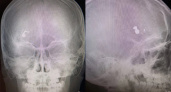

В Саратовской области 12-летний мальчик получил ранение в голову из пневматической винтовки

В Саратовской области врачи спасли ребенка с пулевым ранением головы